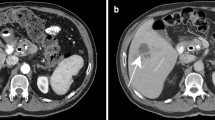

In young children the differential diagnosis of liver lesions includes hemangioendothelioma and hepatoblastoma. Hemangioendothelioma is a benign neoplasm composed of a network of capillary-size endothelium-lined vessels. Patients usually present during infancy with abdominal distension and hepatomegaly. Complications of hemangioendothelioma include congestive heart failure caused by intra-tumoral arterial shunting, anemia, thrombocytopenia, jaundice and bleeding [14]. Hepatoblastoma is a malignant liver tumor that occurs at a median age of 18 months. These children also often present with an abdominal mass and commonly are thrombocytopenic [15]. The serum alpha-fetoprotein can be elevated in both conditions [14].

In adults the addition of microbubble contrast agents has greatly improved the ability to differentiate malignant from benign liver lesions sonographically. Contrast-enhanced sonography is performed in phases similar to three-phase CT and MRI. The arterial phase occurs between visualization of contrast material in the hepatic arteries and contrast opacification of the main portal vein, generally 2–10 s after an intravenous bolus injection. In the arterial phase, the presence of lesional vessels as well as their distribution and morphology can be useful in the diagnosis of liver masses. Hypervascular masses such as hepatocellular carcinoma and focal nodular hyperplasia show linear lesion vascularity. A stellate vascular pattern is often seen in FNH, whereas HCC demonstrates dysmorphic vascularity. Hemangiomas infrequently demonstrate linear vascularity and instead show peripheral puddling of contrast material. Compared to normal adjacent liver, hypervascular lesions such as FNH and HCC appear hyperechoic in the arterial phase, whereas hypovascular lesions such as metastases appear hypoechoic [1, 16].

The portal-venous phase occurs 45–75 s after the arrival of the contrast agent into the field of view. Because the liver is supplied predominantly by the portal vein, the liver shows progressively increased enhancement throughout the arterial phase into the portal venous phase. Malignant lesions, whether metastatic or primary, derive their vascular supply from the hepatic artery and, therefore, appear hypoechoic compared to the normal liver during the portal venous phase. Additionally, malignant lesions usually show washout of contrast material during and after the portal venous phase. Sustained enhancement or increased enhancement beyond the portal venous phase has been shown to be a feature of benign lesions such as hemangioma. Hemangiomas often demonstrate progressive centripedal enhancement with complete filling-in of the lesion after the portal-venous phase, unless there is central scarring or necrosis [1, 16].

In one small study of seven infants with hemangioendotheliomas, Feng and colleagues [14] showed that on three-phase CT and MRI these lesions demonstrate enhancement patterns similar to those described for adult cavernous hemangiomas. Specifically, in the arterial phase peripheral enhancement was seen in 52%, homogeneous enhancement in 48%, fibrillary enhancement in 33% and nodular enhancement in 29%. All lesions <1 cm in diameter demonstrated homogeneous enhancement in the arterial phase whereas larger lesions showed a variety of enhancement patterns. All tumors showed progressively increased enhancement in the portal venous phase. In the delayed phase the majority of lesions became homogeneously enhanced although larger lesions lacked complete enhancement, probably because of central necrosis or fibrosis [14].

Although there have been no reports of the three-phase enhancement pattern of hepatoblastoma, the tumor receives its vascular supply from the hepatic artery and could be expected to have enhancement features similar to those of adult HCC. Given our current understanding of contrast-enhanced US in adult liver lesions it seems reasonable to apply a similar approach to pediatric liver masses. In particular, CEUS might prove useful in distinguishing hepatoblastoma from hemangioendothelioma. Because these lesions can have overlapping clinical and imaging features, CEUS could minimize exposure of these particularly vulnerable young patients to the harmful effects of radiation.